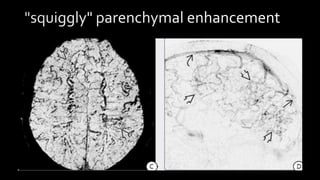

"squiggly" parenchymal enhancement

• #138 Subacute thrombus appears hyper on all sequences….. Clot signal in chronic dst is variable and depends on organization of clot….. LONG STANDING DST MAY DEVELOP SIGNIFICANT COLLATERAL FORMATION THROUGHT MEDULLARY VEINS WHICH IS SEEN AS SQIGGLY PARENCHYMAL

• #139 T2 * SWI shows innumerable prominent tortuous corkscrew squiggly medullary veins throughout both cerebral hemisphers . Venous DSA shows that distal SSS is occluded while proximal and mid seg are patent . Numourous enlarged medullary veins appears to hang in space . This is chronic SSS thrombosis with medullary collateral draingae

• #140 c/o Long standing chronic sss showing thick dural enhancement alonmg tentorium.